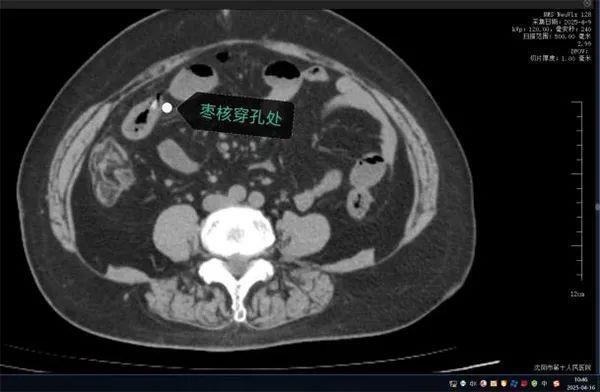

无独有偶,63岁的康阿姨近日因突发“刀绞般”剧烈腹痛,深夜被紧急送往沈阳市第十人民医院。短短数小时内,她出现高热、腹肌强直等弥漫性腹膜炎症状。CT检查显示腹腔游离气体,高度怀疑消化道穿孔。

家属回忆,当天上午康阿姨吃粽子时误吞两颗枣核。医生会诊判断枣核尖端已刺穿小肠,紧急手术取出异物。